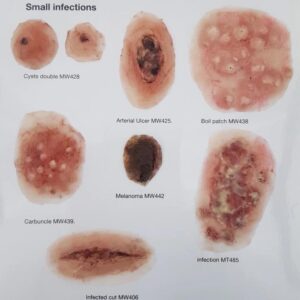

Zestaw ran MP002

Opis

Rany w pełni samoprzylepne, a dla uzyskania lepszej przyczepności można nakładać za pomocą kleju żelowego.

-łatwe do nakładania i usuwania bez pozostawiania śladów

-wielokrotnego użytku

-można myć ciepłą wodą

Informacje dodatkowe

Kategoria: Rany naklejane